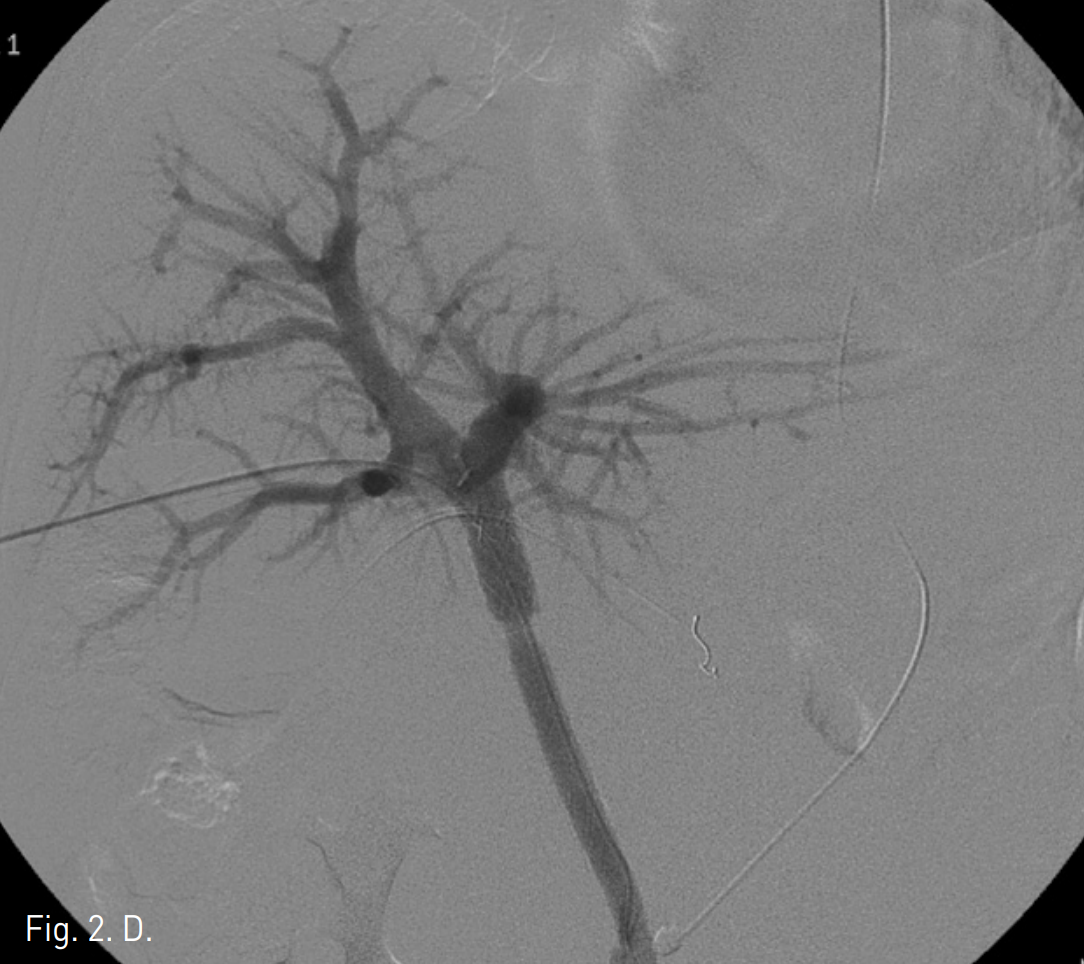

초음파 유도 하에서 우측 문맥을 20G Chiba needle을 이용해 직접 천자한 후 문맥 조영 영상에서 문맥부 합성혈관의 혈전성 폐색을 확인하였다(Fig. 2A). 5F Davis catheter (Cook, Bloomington, IN, USA)와 urokinase (200K unit)를 이용한 혈전용해술, 7F Sheath catheter (Cook, Bloomington, IN,USA)를 이용한 흡입 혈전제거술과 stent를 이용한 치료를 계획하였다. 혈전용해술 및 흡입 혈전제거술을 시행한 후 문맥의 혈류가 회복되었으나 이 과정에서 간 내 문맥(intrahepatic portal vein)에 혈전성 색전에 의한 것으로 보이는 간 내 문맥의 충만결손이 발생하였고(Fig. 2B), 이에 대해 다시 흡입혈전제거술을 시행하여 문맥의 흐름을 원활히 하였다. 이후 자가팽창형 스텐트(10mm x 80mm)(S&G biotech, Seoul, Korea)를 합성혈관의 근위부 및 원위부 접합부를 모두 포함하도록 설치하였다(Fig. 2C), 스텐트를 위치시킨 후 시행한 문맥조영술에서 간 내 문맥의 충만결손이 사라지고 스텐트 삽입 부위의 문맥의 혈류가 원활하며 출혈 등의 시술 후 부작용이 없음을 확인하고 시술을 종료하였다 (Fig. 2D).

D. Post stenting portogram shows patent portal vein and superior mesenteric vein without intrahepatic embolism.